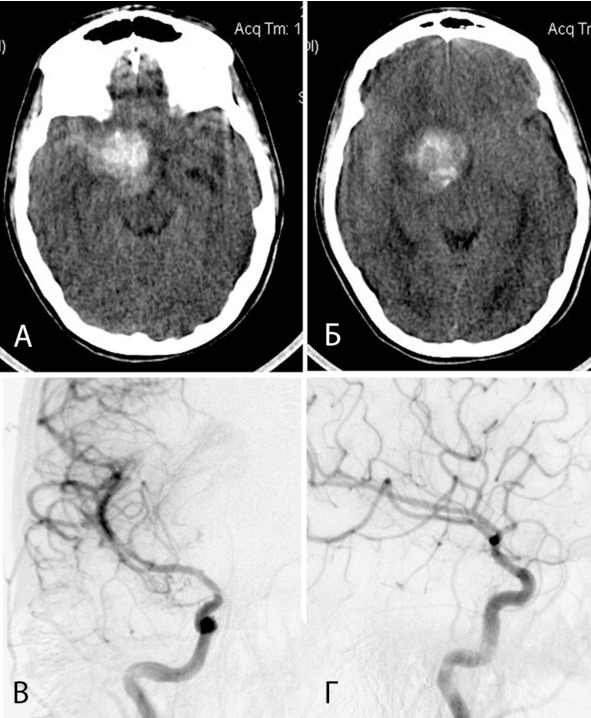

Из анамнеза известно, что в течение нескольких лет пациентку беспокоили головные боли. В октябре 2006 года эпизод сильной головной боли, выраженной общей слабости с подъемом АД до 150/90 (клиническое САК). Осмотрена бригадой скорой помощи, не госпитализирована. В течение недели симптоматика регрессировала. Ухудшение состояния 28.10.2007, когда у больной вновь внезапно появилась головная боль, произошла потеря сознания. Бригадой скорой помощи доставлена в детскую городскую клиническую больницу. Согласно данным медицинского осмотра при поступлении уровень сознания был на уровне глубокого оглушения, выявлялась менингеальная симптоматика, анизокория за D> S, отсутствие фотореакции OD, левосторонний глубокий гемипарез. При КТ от 28.10.2007 выявлено САПК с гематомой в базальных отделах правой лобной и височной долей, гипоталамической области, кровь в латеральной щели, субарахноидальных пространствах справа, смещение срединных структур на 6 мм (рисунок 10: А, Б). Больная переведена в НИИ Нейрохирургии. При поступлении на фоне выраженной общемозговой симптоматики и снижения уровня бодрствования (умеренное оглушение) выявлялся парез III нерва справа, центральный парез VII нерва слева, умеренный левосторонний пирамидный гемипарез. Имелась мягкая орально-стволовая симптоматика. При ТК УЗДГ выявлено умеренное ускорение кровотока по правой СМА. На тотальной ангиографии от 01.11.2007 данных за сосудистую патологию не выявлено (рисунок 10: В, Г). За время пребывания в институте отмечалась значительная положительная динамика в неврологическом статусе. Сохранялись парез III нерва справа, центральный парез VII нерва слева, легкая левосторонняя пирамидная симптоматика. По данным КТ от 31.10.2007 объем гематомы в подкорковых структурах справа и в базальных отделах мозга оставался прежним, сохранялось смещение срединных структур и сдавление желудочковой системы. По данным ультразвукового обследования отмечался регресс вазоспазма. Для продолжения лечения переведена в стационар по месту жительства. Рекомендована повторная АГ через 3—4 месяца.

Рисунок 10. КТ в аксиальной проекции на 4-й день после кровоизлияния (А, Б) и правосторонняя каротидная АГ в прямой и боковой проекции (В, Г). На КТ выявляется гематома в базальных отделах лобной и височной долей, гипоталамической области, кровь в цистернах основания и правой латеральной щели. На АГ данных за патологическую сосудистую сеть не выявлено.